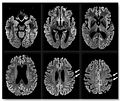

Creutzfeldt-Jakob disease

Bò điên là một rối loạn thoái hóa não dẫn đến chứng mất trí nhớ và cuối cùng là tử vong.